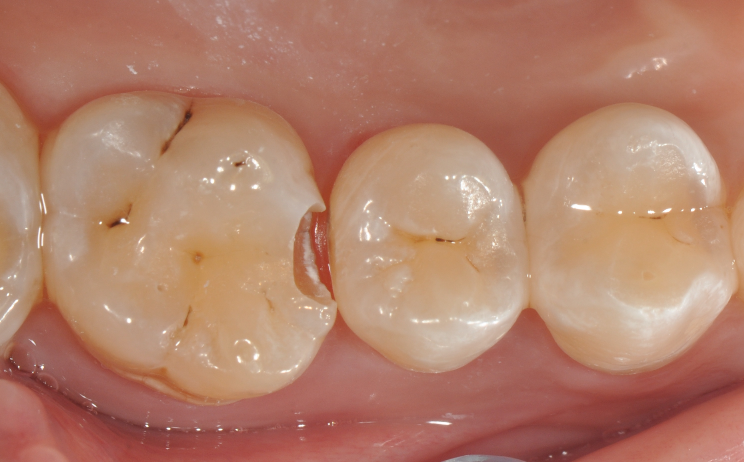

牙医-马小寒【实操病例】

右上6号牙位的近中,可见隐约龋坏